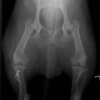

左後肢の挙上を主訴に来院されました。触診にて両関節の前方引き出し兆候、両膝蓋骨の内方脱臼を認めました。関節液検査より免疫介在性多発性関節炎は否定的でした。レントゲン検査にてfat pad signを伴う関節炎が認められたことから、前十字靭帯断裂と膝蓋骨内方脱臼(左GradeⅢ 右GradeⅢ〜IV)併発と診断し、手術を行いました。

術前左後肢側面像

術前正面像

術前のTPAは左後肢33.1°右後肢26.8°でしたがTPLO実施により左後肢5.5°右後肢12°に矯正されました。